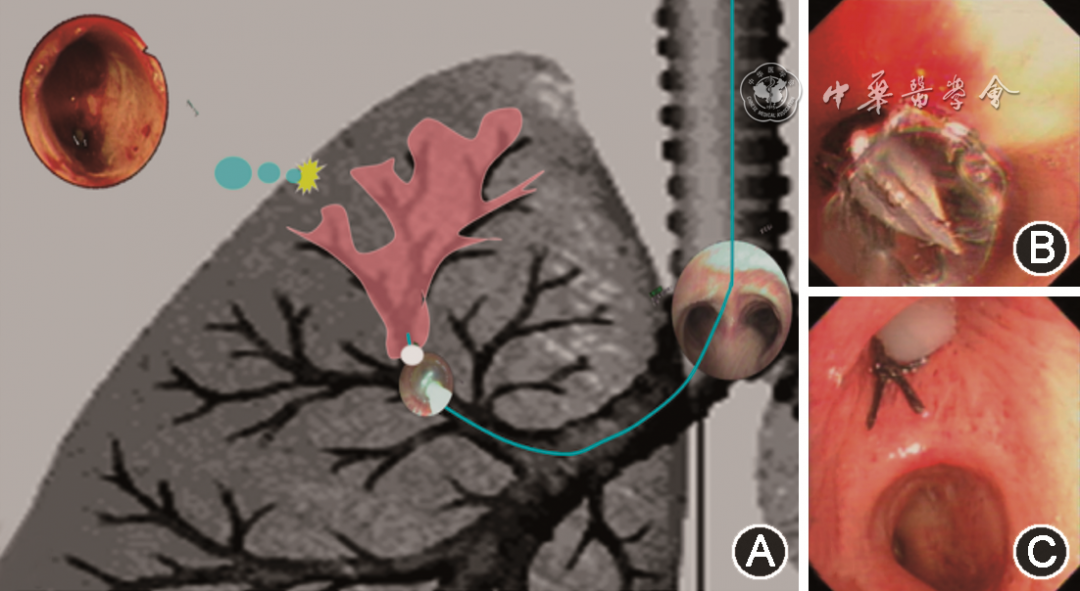

(二)责任引流支气管的封堵

当责任引流支气管确定之后,可选择不同的封堵方法将责任引流支气管暂时性封堵。SBO治疗难治性气胸的基本原理是将责任引流支气管暂时性封堵,使所属肺叶或肺段的胸膜瘘口停止漏气并愈合,因此封堵应该是暂时性的(可恢复性的),以免导致永久肺不张。封堵方法总体上可归纳为封堵剂封堵及封堵器封堵两大类(图3)。

abb892caf7341f51ef68624cb80cebec.png

图3 不同的气胸封堵方法示意图,图A为自体血+凝血酶封堵,图B为单向活瓣封堵,图C为支气管塞封堵